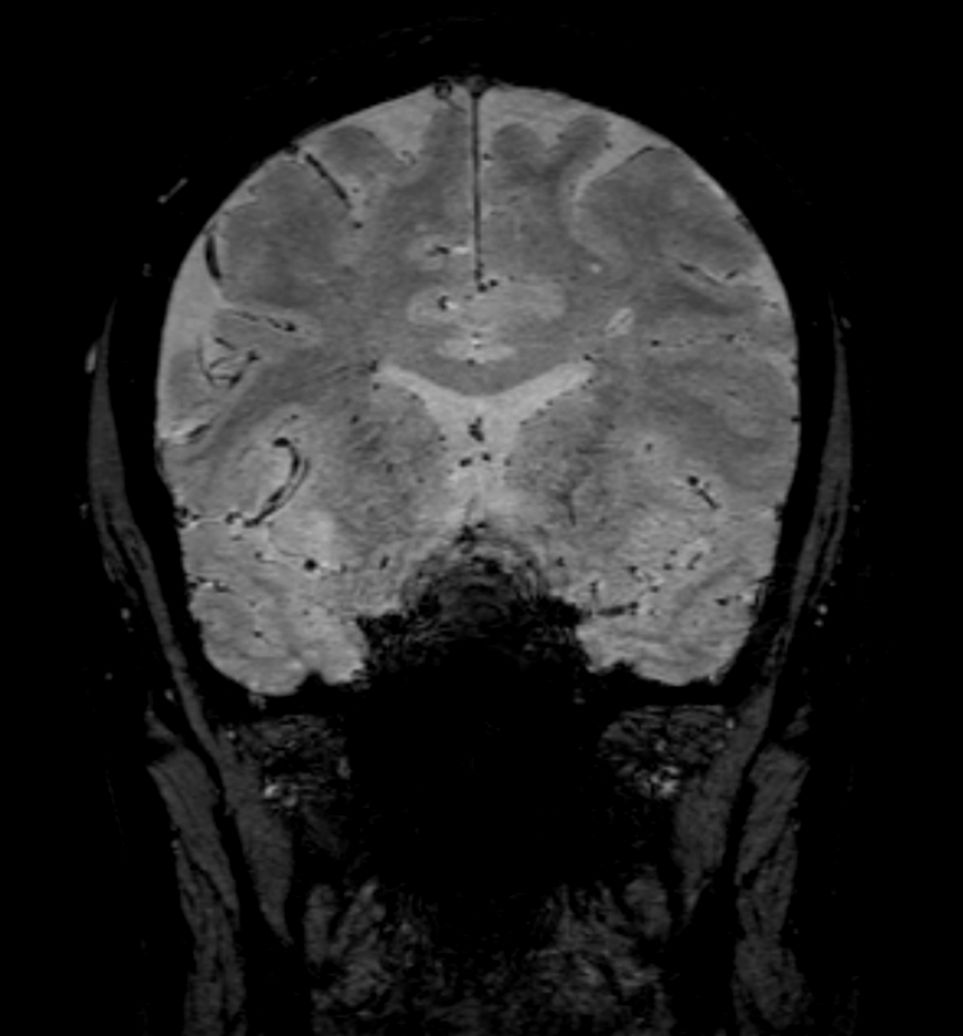

SWI sequence has a high sensitivity to enhance contrast for deoxygenated (venous) blood or calcium deposits. This may help, when used in combination with other clinical information, in the diagnosis of various neurological pathologies. 3D imaging lets you acquire high resolution data in multiple directions in one scan. Isotropic voxel size enables reformats in any plane without loss of resolution. FLAIR* requires offline post processing combining the contrast of 3D FLAIR and 3D SWI EPI into a single image. This enables the visualization of Central Vein Sign, mapping subcortical veins onto 3D FLAIR contrast images.